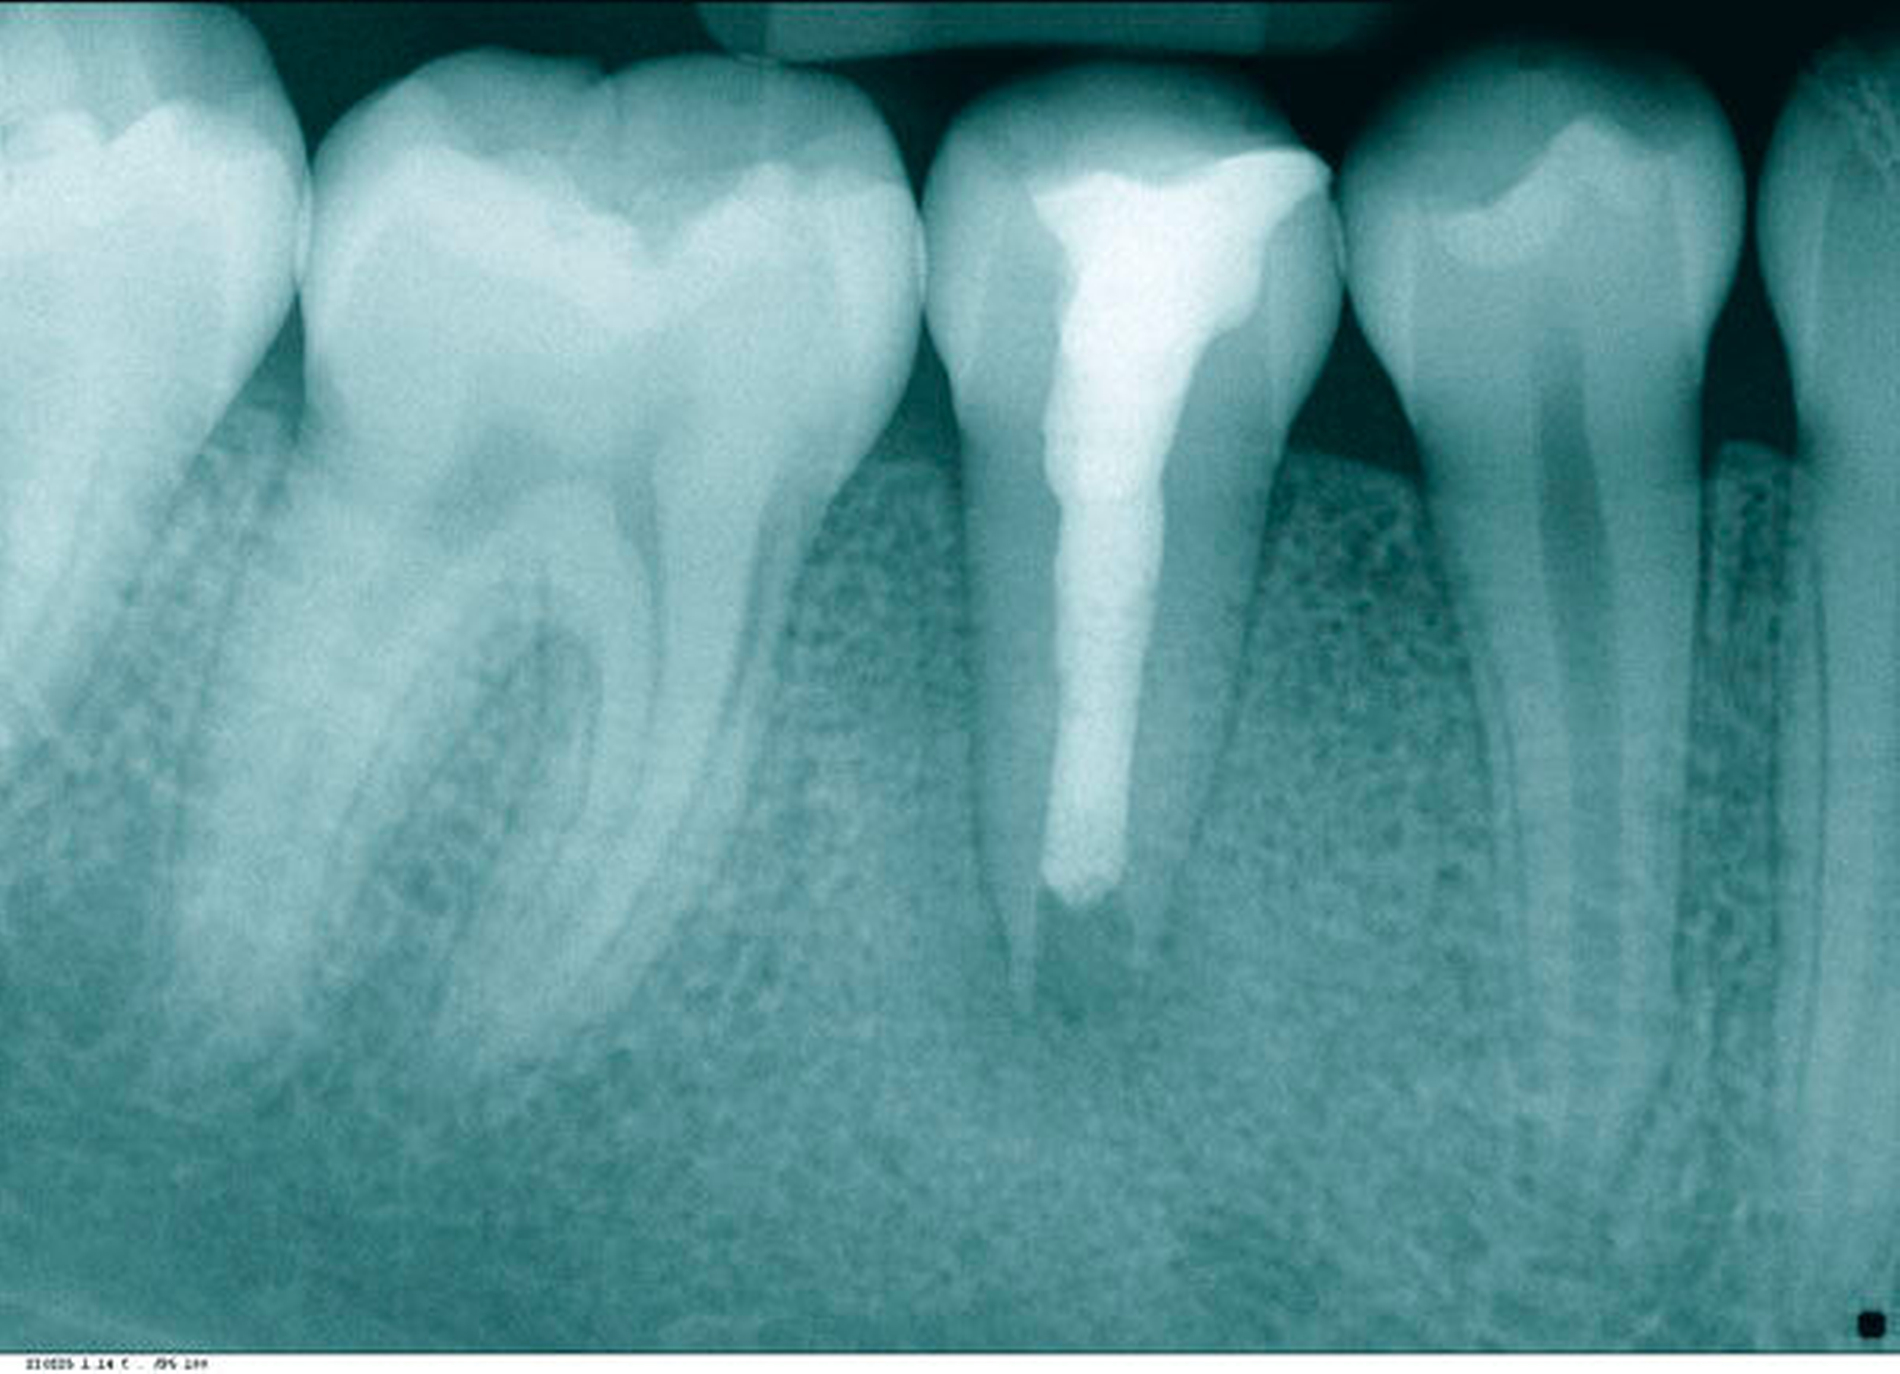

Anschließend wurde der Rest des Kanals adhäsiv verklebt und indirekt mit Komposit versorgt. Eine Kontrollaufnahme wurde angefertigt (Abbildung 9). Abbildung 10 zeigt die postendodontische Versorgung des Zahnes.

Die Patientin klagte weder über eine Symptomatik, noch zeigten sich Entzündungszeichen im Verlauf. Die sporadischen Schmerzen und das Druckgefühl im Kiefer waren beim ersten Kontrolltermin nach vier Wochen gänzlich abgeklungen. Der Klopfschall war unauffällig, der Zahn reagierte nicht auf Perkussion und das Vestibulum war schmerzfrei bei Palpation. Nach vier Monaten erfolgte ein Verlaufsröntgenbild (Abbildung 11), bei dem bereits eine Hartsubstanzausbildung und ein fast vollständiger Rückgang der Läsion zu erkennen sind. Nach zehn Monaten wurde ein weiteres Verlaufsröntgenbild angefertigt (Abbildung 12). Die Läsion scheint vollständig rückläufig und mit Hartgewebe ersetzt zu sein. Die radiologische Nachkontrolle nach 18 Monaten zeigt eine deutliche Dickenzunahme des Dentins im Vergleich zur Ausgangssituation und stabile periapikale Verhätnisse (Abbildung 13). Der Zahn ist nach wie vor symptomfrei und in situ.